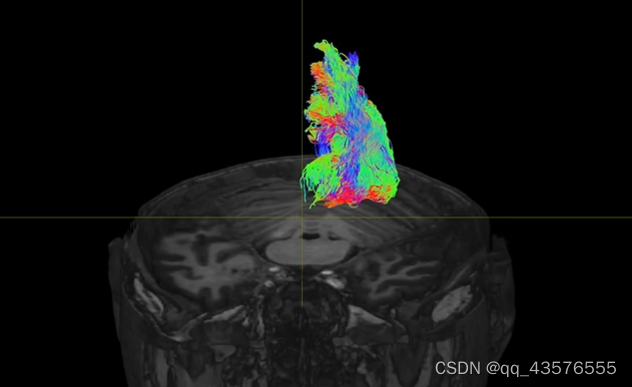

tckgen: [100%] 367099 seeds, 259465 streamlines, 200000 selected将得到的追踪像 .tck文件和结构像T1w放在mrview中打开,选择Tractography选项,就得到了对比图如下,可以选择不同的切面

基于兴趣区的追踪与之类似,改变某些参数即可,下图为视觉纤维束